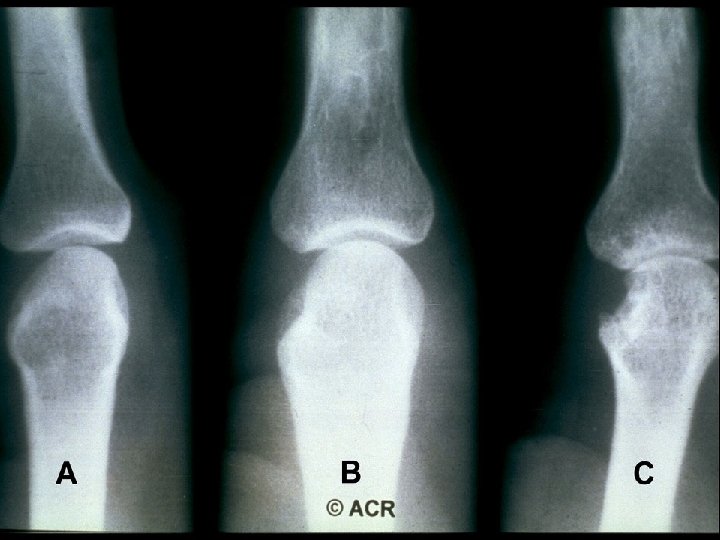

Prognostic Markers in RA · Definitive Markers - Subcutaneous nodules - Detection of erosions on x-ray

Joint Erosions Occur Early in RA Maximum % Joints Affected · Up to 93% of patients with <2 years of RA may have radiographic abnormalities · Erosions can be detected by MRI within 4 months of RA onset Hand MTP All · Rate of progression is significantly more rapid in the first year than in the second and third years Year Fuchs HA et al. J Rheumatol. 1989; 16: 585 -591. Mc. Queen FM et al. Ann Rheum Dis. 1998; 57: 350 -356. van der Heijde DM et al. J Rheumatol. 1995; 22: 1792 -1796.

Sharp Scores of Radiographic Progression Erosion scores · 17 joints of each hand/wrist · 6 joints of each forefoot · Scale: 0– 5; Total score: 0– 230 Joint space narrowing (JSN) scores · 16 joints of each hand/wrist · 5 joints of each forefoot · Scale: 0– 4; Total score: 0– 168 Total Sharp score · Add erosion and JSN scores · Total score: 0– 398 Sharp JT, et al. Arthritis Rheum. 1985; 28: 1326– 1335 van der Heijde DM, et al. J Rheumatol. 1995; 22: 1792– 1796.